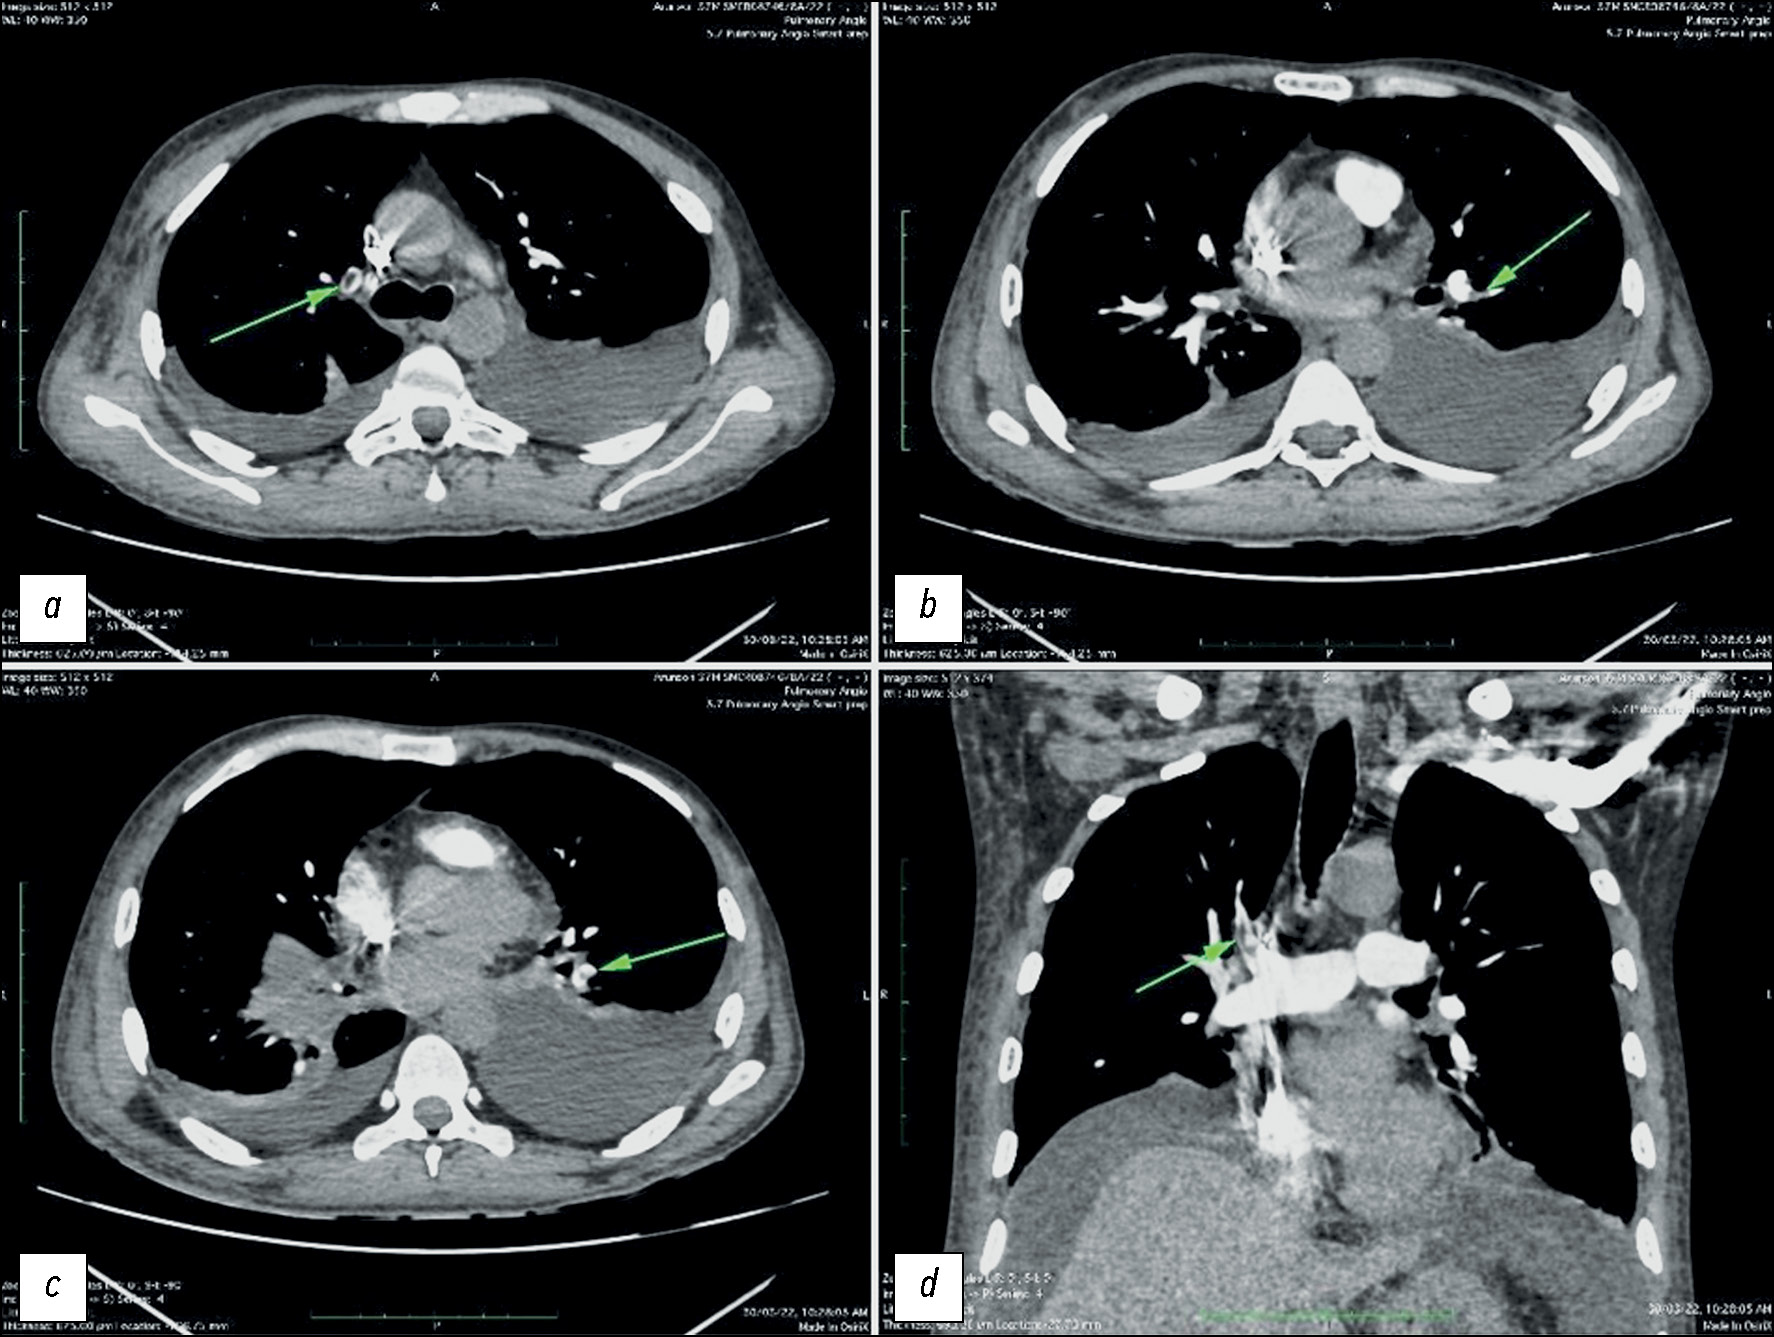

BACKGROUND: The coronavirus disease pandemic (COVID-19), caused by severe acute respiratory syndrome coronavirus 2, has led to significant morbidity and mortality worldwide since its emergence in 2019. Although primarily a respiratory illness, COVID-19 can also affect other organ systems, including the vascular and gastrointestinal systems. COVID-19 is linked to both venous and arterial thrombosis, and numerous studies have indicated a heightened risk of pulmonary embolism. Autopsies have revealed pulmonary vasculature thrombosis and bowel ischemia in patients with COVID-19.

AIM: To assess radiological pulmonary vascular changes, specifically pulmonary embolism, and gastrointestinal changes in patients with COVID-19 referred to a tertiary healthcare center in Chennai, India.

MATERIALS AND METHODS: Computed tomography pulmonary angiography and contrast-enhanced computed tomography of the abdomen were conducted in 100 patients with COVID-19 who met the selection criteria. A radiologist with 5 years of experience evaluated pulmonary vascular and bowel changes. Subsequently, statistical analysis was performed to determine the significance of the relationship between patients with COVID-19 and the occurrence of pulmonary vascular and bowel changes.

RESULTS: In this study, 11 patients exhibited pulmonary thromboembolism, and 7 showed significant bowel changes such as bowel wall thickening, mesenteric ischemia, and omental infarction, indicative of potential gastrointestinal involvement of patients with COVID-19. A positive correlation was found between pulmonary embolism prevalence in patients with COVID-19. Pulmonary embolism was diagnosed at a mean of 11 days from disease onset. Of the 24 patients with severe acute respiratory illness, 7 showed pulmonary embolism, detected by computed tomography pulmonary angiography. In addition, of the 10 patients on mechanical ventilation, pulmonary embolism was found in 7. Among the seven patients with bowel changes, four had pulmonary embolism, as detected by computed tomography pulmonary angiography, indicating a significant association between the two concomitant complications. The observed bowel changes were attributed to intravascular thrombosis.

CONCLUSIONS: Based on our findings, pulmonary emboli and bowel changes often occur in patients with COVID-19. Multivariate analyses also revealed a connection between invasive mechanical ventilation and pulmonary embolism. The results indicate that patients with severe COVID-19 may also experience concurrent acute pulmonary embolism. Thus, for these patients, the use of contrast-enhanced computed tomography instead of standard non-contrast computed tomography may aid in treatment decision-making.